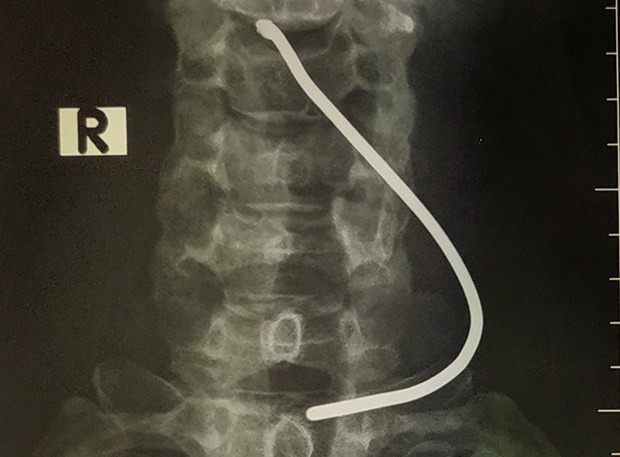

Người bệnh được chuyển lên bệnh viện đa khoa tỉnh trước khi chuyển Bệnh viện Hữu nghị Việt Đức vào 20 giờ ngày 24/3. Tình trạng của bệnh nhân khi ấy tỉnh táo, vùng cổ có vết thương thanh quản 0,5cm, tổn thương sụn giáp.

Thạc sỹ Dương Ngọc Thắng - Trung tâm Tim mạch và Lồng ngực (Bệnh viện Hữu nghị Việt Đức) đã tiến hành phẫu thuật thăm dò vết thương cho bệnh nhân T, lấy dị vật, khâu vết thương sụn giáp. May mắn cho bệnh nhân, thanh sắt xuyên qua sụn giáp, đi vào thanh quản nhưng không tổn thương dây thanh âm.